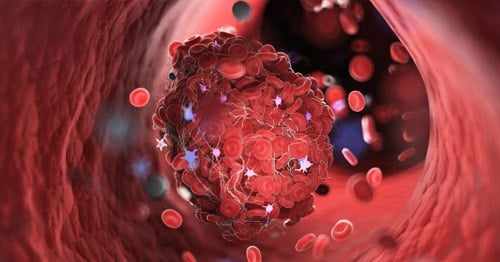

Antiphospholipid syndrome is a systemic autoimmune inflammatory disorder in which a person’s immune system makes antibodies that can cause the formation of blood clots in the blood vessels as well as pregnancy problems. Blood clotting (thickening of the blood) is a normal function of the body. It is what stops the bleeding when we get a cut. But blood clots that form inside the blood vessels are dangerous, and the overactive blood clotting associated with APS can cause life-threatening health problems.

Antiphospholipid antibody (aPL) describes antibodies that attack certain proteins that bind the phospholipid cell walls of blood cells located on the inner layer of the arteries or veins. These antibodies are generally detected by three tests, namely: lupus anticoagulant (LA), anticardiolipin antibody (aCL), and anti-Beta-2-glycoprotein-I antibody (aβ2GPI). All of these create enhanced risk for blood clotting.

Blood clots in the arteries or veins (sometimes on a microvascular level) caused by antiphospholipid antibodies can create a deep vein thrombosis (DVT) or pulmonary embolism as well as high blood pressure, heart attack, stroke, miscarriages, and many other problems. APS blood clot health complications include the following: